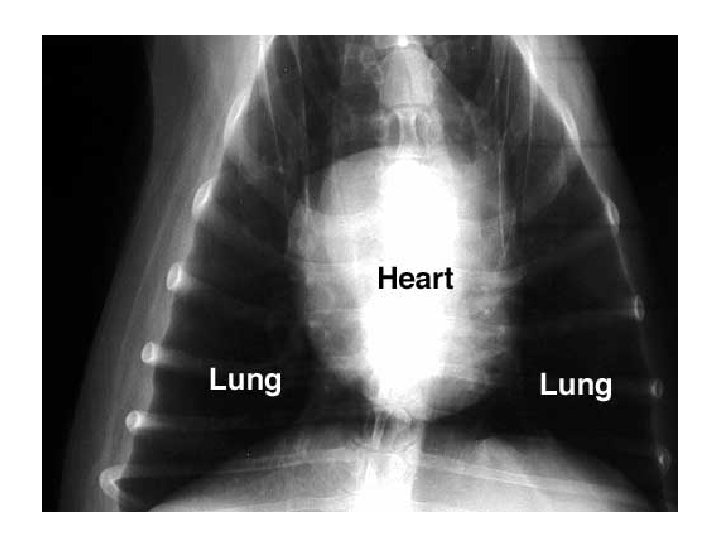

The lungs are the primary structures of the respiratory system. The lungs occupy almost the entire thoracic space. Each lung contains millions of aveoli and capillaries.

The lungs are encased in a serous membrane called the visceral pleura. The thoracic cavity is lined with another membrane called the parietal pleura. These membranes reduce the friction during repiration

The space between these membranes is called the pleural cavity or potential space.

The thorax (chest cavity) is lined with a membrane similar to the covering of the lungs. This allows the lubrication of both surfaces during respiration This membrane is divided into the: *right pleural cavity *left pleural cavity *mediastinum

The mediastinum contains the heart, thymus, esophagus, trachea, bronchi, nerves, arteries, veins and lymphatic vessels.